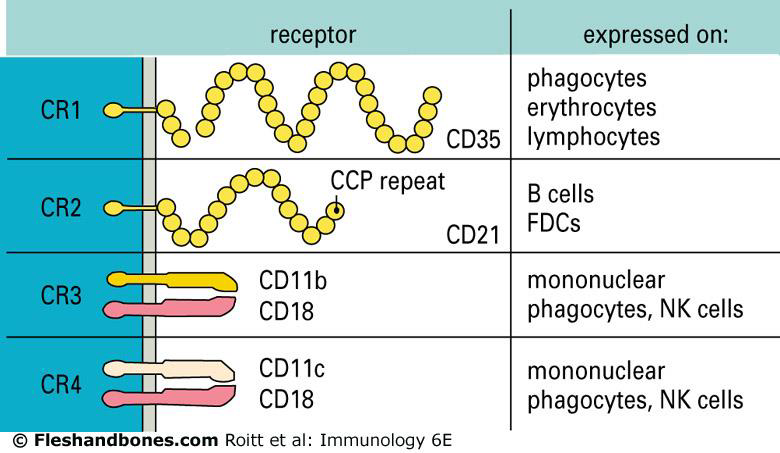

補體受體 (CR)

Factor I 和 CR1 會切斷 iC3b,形成 C3c和 C3dg,而 C3dg 會由CR2 辨認。

- CR1

- 結合 C3b

- 需要 C5a 活化,促進吞噬、調理

- CR2: B cell, EBV(Epstein-Barr virus) receptor

- 結合 C3dg

- CR3, 4

- 認 iC3b

- CR3 是 integrin